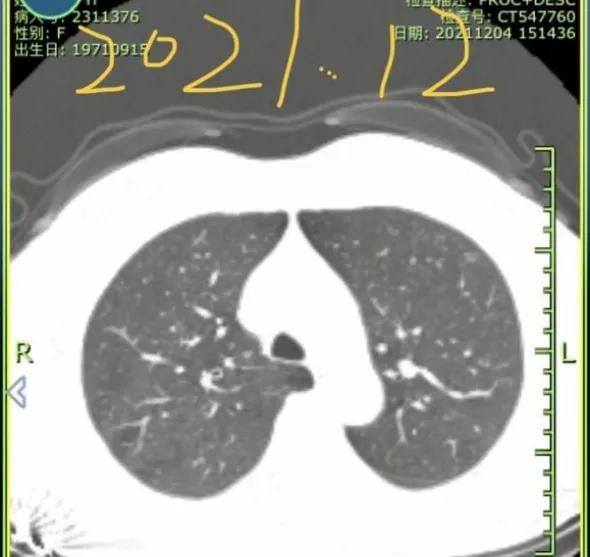

2021年12月,我母亲做CT查出左肺上下叶各有一磨玻璃结节,大小均为6-7mm,医生让3-6月复查。今年6月复查,报告显示有一个侵犯胸膜,大小长至10mm。医生看影像后初判微浸润,让手术切除。慕名而来,恳请戴主任帮忙看看,我们好心安。

一个安徽的宝妈,在6月的时候向我求助:她的妈妈CT查出了两处磨玻璃结节,尺寸都在6-7mm。后来随访过程中发现一个结节增长到了10mm,并且出现了侵犯胸膜的情况,加上省会医生给的一个“微浸润”,这下让这位宝妈异常焦急。再次向我求助,想来重庆新桥进行手术。(插一句,我对宝妈这样质实的孝,异常钦佩;对于宝妈的要求,我一定是安排好所有的绿色通道,亲自处理的)。手术很成功,虽然难度极大(全胸腔粘连),但是考虑到患者未来恢复,和你需要照顾孩子的实际情况,我还是坚持全程微创,没有开胸。手术即治愈,未来慢慢恢复即可,不用担心。